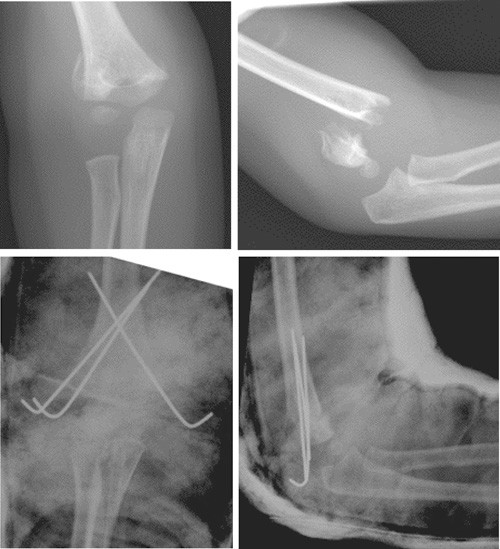

Suprakondylære humerusfrakturer hos barn klassifiseres i dag etter Gartlands klassifikasjon (fig 1) (8). Denne klassifikasjonen har god intra- og interobservatør reliabilitet (9). Gartland type 1 er en udislokert fraktur. Type 2 er en dislokert fraktur med intakt bakre cortex. Disse frakturene er av ren ekstensjonstype, ettersom den posteriore cortex stabiliserer bruddet i rotasjon. Type 3 er en helt dislokert fraktur uten kontakt mellom bruddfragmentene og har ofte rotasjonsfeilstilling i tillegg til ekstensjonsfeilstilling. Disse bruddene er assosiert med nevrovaskulær skade. Det er rapportert pulsløs ekstremitet i opptil 20 % av Gartland type 3-frakturer (4).